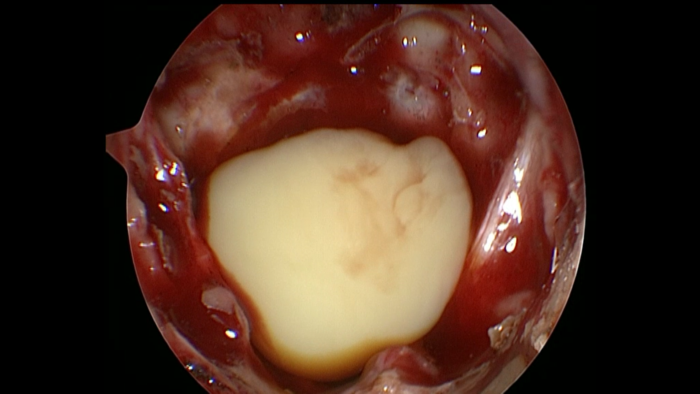

豆腐渣样,为白色粉膏状皮脂和破碎的皮脂腺细胞,常继发感染,形成脓肿